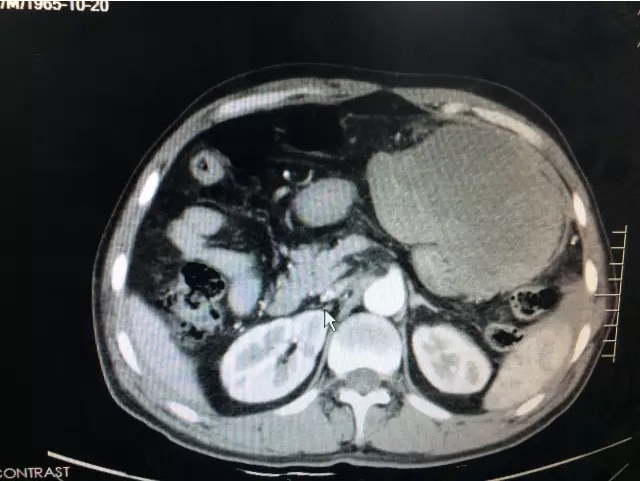

科主任崔小兵主任医师诊视患者后指出:“诊断考虑胃大弯占位:间质瘤可能,目前患者腹痛剧烈,有腹膜炎体征,不排除有肿瘤破裂可能,急查腹部CT,完善相关化验检查,尽早手术。”紧急动员之后,管床医生及护士密切合作,启动急危重症患者工作流程,全程陪同外出检查,结果提示:1.胃巨大占位;2.盆腹腔大量积液,考虑胃间质瘤破裂;3.失血性休克代偿期(患者心率102次/分,血压105/74mmHg)。主任当机立断,要求紧急联系麻醉科、输血科,拟于假期前一天急诊手术探查。

术前CT提示胃巨大肿瘤占位